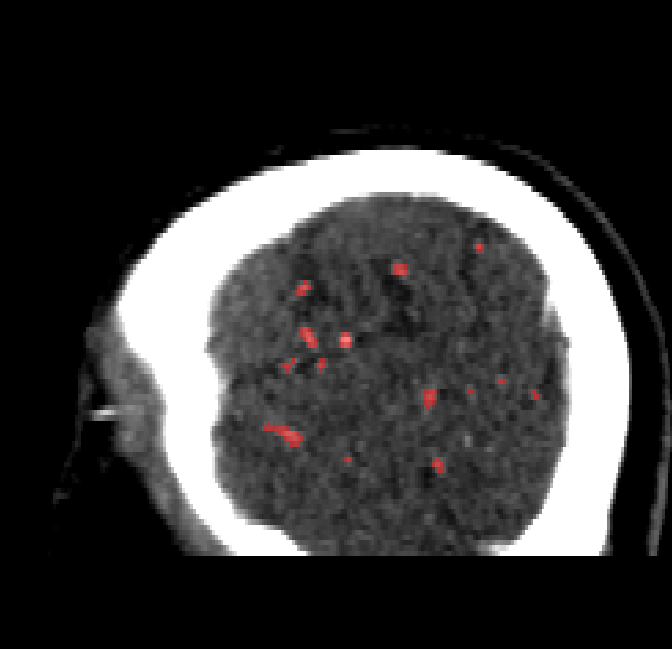

Qualitative Results

After fine-tuning, the two pre-train conditions appear to have little or no difference in terms of qualitative performance at the vessel segmentation task. However, when compared to the models trained only on real data, there are noticeable differences. Throughout Figures 4.3-4.9, the model pre-trained on scans with original CT noise is to be taken as representative of segmentation performed by the Perlin noise pre-training condition. Images showing the hand-labeled ground truth, as well as the unlabeled slice, are presented for comparison.

Figure 4.5: Segmentations on a central slice. Unaltered image (left). No pretrain model (mid-left). Fine-tuned model (mid-right). Hand-labeled ground truth (right).

For vessels in the center of the head, all model types appear to accurately segment vessels. In certain cases, the models appear to learn to correctly avoid segmenting pieces of bone that could, in terms of shape and contrast, easily be confused with large vessels. An example of this can be seen in the frontal section of Figure 4.6.

The models appear to have a hard time segmenting vessels close to the skull surface. The model trained exclusively on patient data appears to struggle far more for these types on conditions than the fine-tuned models. Figure 4.8 shows an example of the fine-tuneds model having close to no trouble segmenting vessels near the left side of the skull, while the baseline model suffers heavily from false negatives. To lesser degree, this effect can also be observed in the frontal lobe of Figure 4.9 In the other hand, Figure 4.7 presents an example of both models failing to segment vessels near the top of the skull.

In the other hand, it should be noted that fine-tuned models suffered from false positives more often than models with no pre-training. The fine-tuned models appeared to occasionally segment regions near the skull, which although similar in intensity to vessels, had no resemblance in terms of shape. Examples of this are seen in Figure 4.4 near the occipital bone and near the right temporal bone. Examples of oversegmentation were observed to happen commonly around the internal carotid arteries. This is likely due to the amount of contact surface between the artery and the surrounding bone. There was also a tendency for all model conditions to segment bone regions that were similar in shape to large vessels (Figures 4.3 and 4.4). Bone structures in such regions have similar pixel intensities to the arteries transporting contrast material, which could explain the source of confusion for a model.

To our surprise, the models were able to occasionlly segment the shape of the internal carotid arteries correctly despite no boundary being visible to the naked eye between the vessel wall and the surrounding bone structure. An example of this can be seen in the fine-tuned model in Figure 4.3.